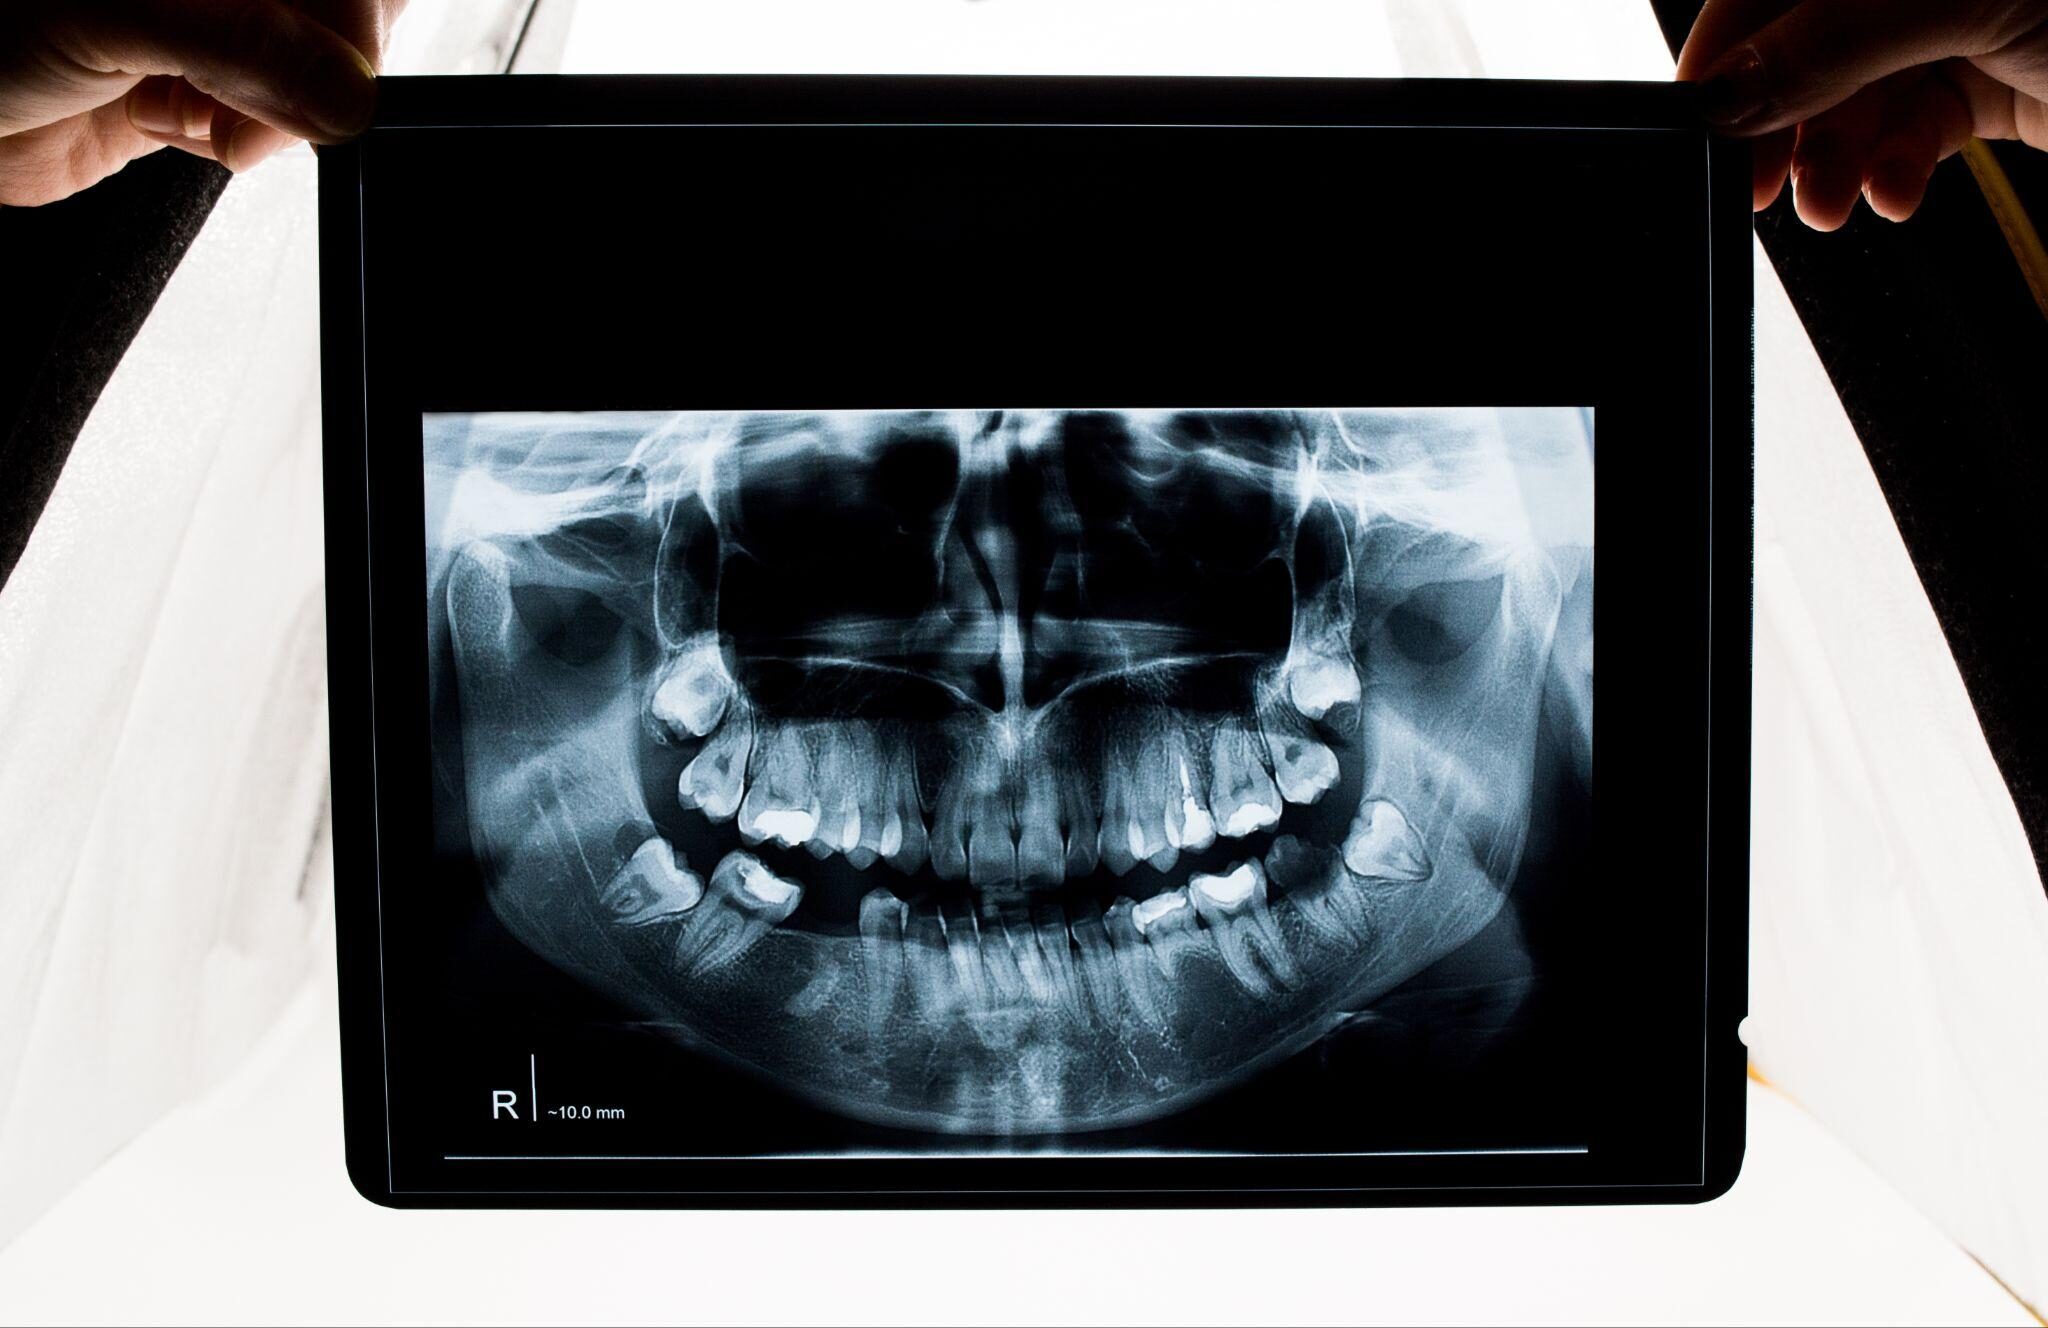

外科矯正とマウスピース併用治療を行う場合、まずは顔全体のバランスや顎の位置、咬み合わせの状態を詳細に確認します。CT撮影やセファログラム(頭部X線)、歯列模型などを用いて、骨格構造と歯並びの関係を精密に分析するのが最初のステップです。

そのうえで、マウスピース矯正がどの範囲まで適用できるかを判断し、術前矯正・術後矯正のどの段階で活用できるかをシミュレーションします。歯の移動量や顎の骨格的ずれの程度を評価し、治療全体の流れを設計します。